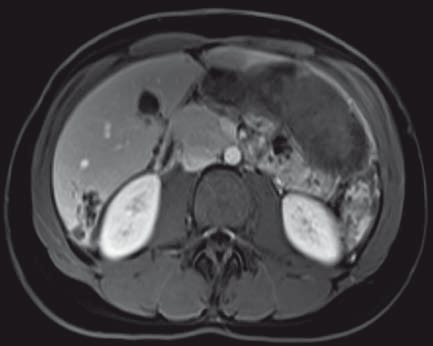

Figure 7 : Coupe axiale T1 avec saturation de la graisse après injection IV de chélates de gadolinium

Description de l'IRM hépatique

• Multiples petits kystes confluents en hypersignal T2, hyposignal T1, de paroi fine se rehaussant après injection de produit de contraste.

• De siège intra-hépatique (segment VI), sur foie sain.